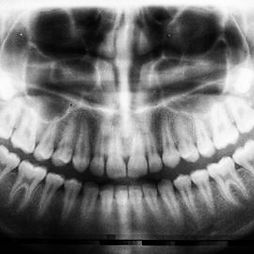

Modern Technology

Our office is equipped with modern technology to ensure that our patients receive the most advanced dental treatments available in a clean and calm environment.